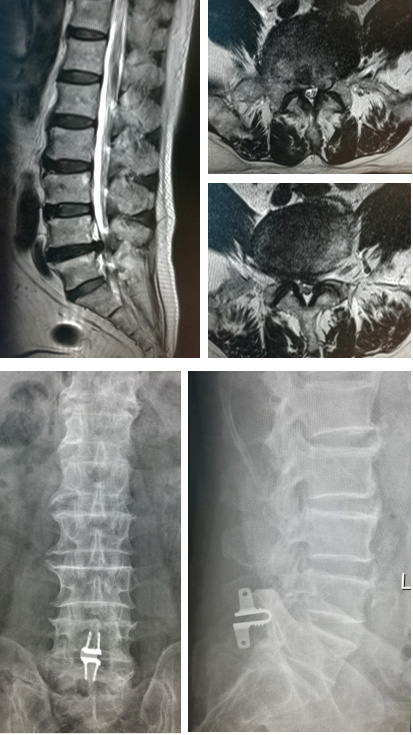

病例 2

患者周某,女 47岁,主因“腰背部疼痛放射至左下肢1年,加重3周”入院,诊断为腰椎管狭窄症,接受L5/S1 TLIF+L4/5 Coflex手术治疗,术后腰腿疼痛明显缓解。